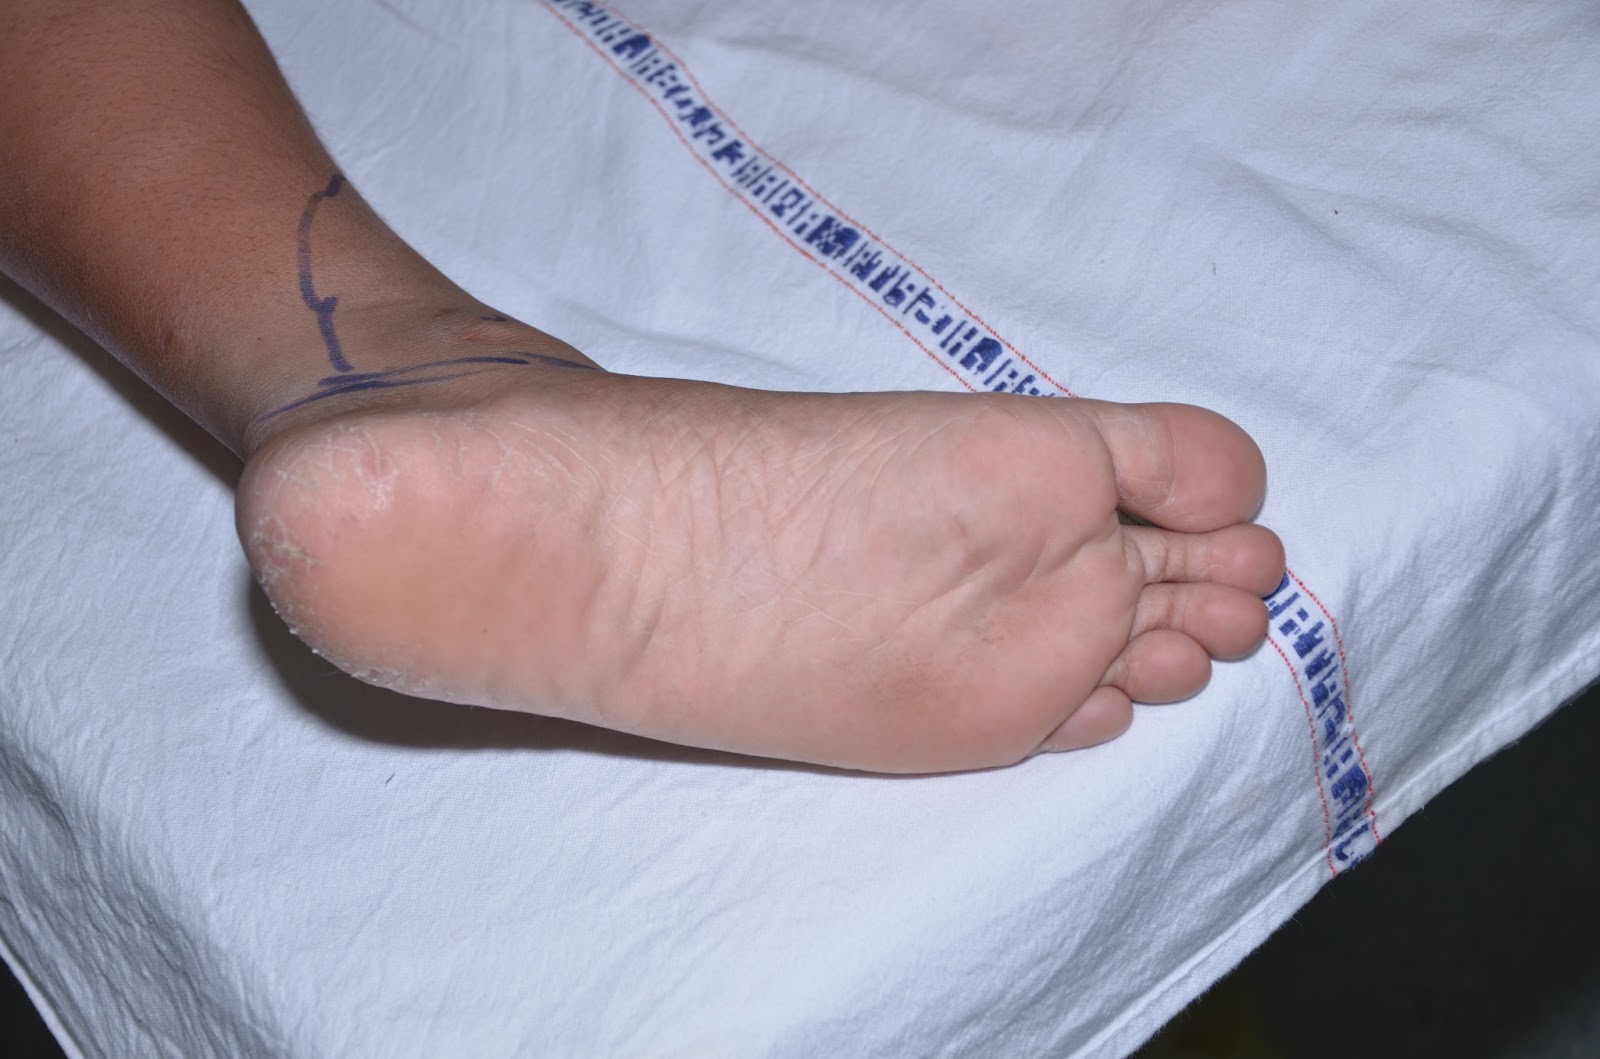

From sciencephoto.com

Bruised foot following crush injury Stock Image M330/1721 Science Foot Pain After Crush Injury Choose which area of your foot hurts most to find out about treatments, when to get medical help and possible causes. These wounds are usually very serious, involving many fractures. Find out about foot injuries, including advice, care plans, treatments, and rehabilitation steps to promote optimal healing. The physician will perform a. People that have suffered crush injuries of the. Foot Pain After Crush Injury.